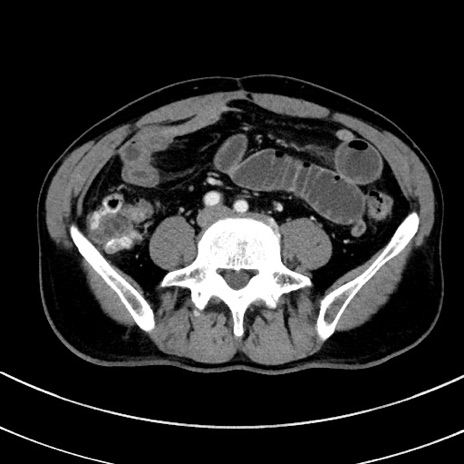

冠状断像

【症例】 60歳代男性

【主訴】 黒色吐物

【現病歴】 4日前から嘔気自覚、2日前の朝食後にも嘔気あり、自分で手で嘔吐反射起こし嘔吐したところ血が混ざっていたため受診。

【既往歴】 5年前汎発性腹膜炎を伴う急性虫垂炎で手術、高血圧、前立腺肥大症、高脂血症

【身体所見】 腹部正中に手術癩痕あり 腹部平坦・軟圧痛なし膨満感あり

【データ】WBC 8400、CRP 4.54